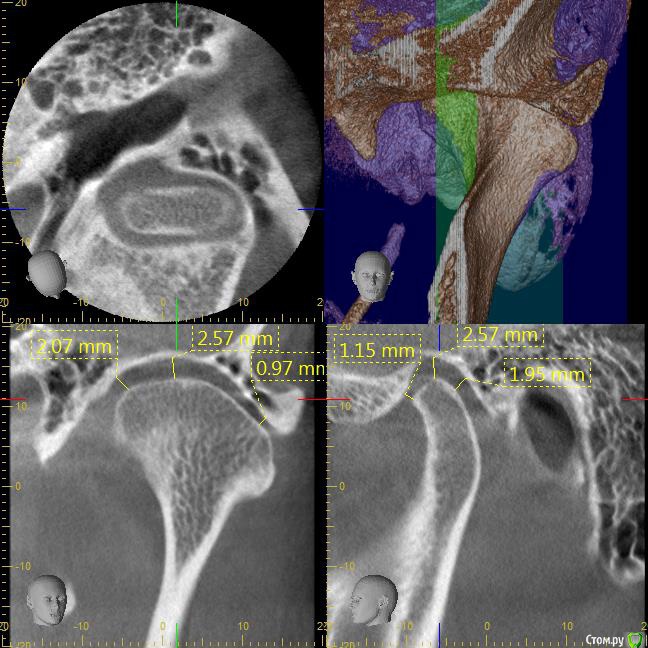

После лечения жевательных зубов на нижней и верхней челюсти начался дискомфорт в прикусе. Врач подшлифовал пломбы, начались боли в мышцах. Попробывал завысить, стало еще хуже. Через месяц начались щелчки с левой стороны, боли усиливались в районе жевательных мышц. Пробывали капы, результатов не давало. Сейчас не могу ни переживать толком еду, спать вообще не удобно. челюсть в обычном положении зафиксировать не могу, жевательных мышц совсем не чувсвую,разговаривать тоже не удобно, слюну ковтать трудно.Сильно напряжены мышцы возле носа, сзади головы и шеи, раслабить никак не могу. Начались сильные головные боли, боли в шее, в левой лопатке.  Сделали мрт шейного отдела, показало деформация шейного отдела и грыжи. Стоматологи говорят что это из-за прикуса. К кому обратиться помогите,Есть фотография до лечения, прикрепляю.

КТ даёт лишь информацию относительно костных структур сустава, а хотелось бы увидеть что там со связками, но для этого нужно МРТ. Со стороны костных структур я не увидел каких-то критических изменений, за исключением может быть ремоделирования суставных поверхностей.